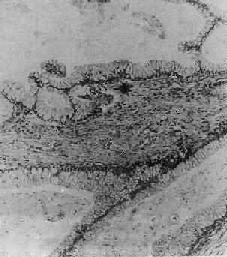

connective tissue diseases

以疏鬆結締組織粘液樣水腫及纖維蛋白樣變性為病理基礎的一組疾病。最早認為主要是膠原纖維發生纖維蛋白樣變性所致,故稱為瀰漫性膠原病或膠原血管病,以後認為主要病變不僅限於膠原纖維,而改稱為結締組織病。病因不十分清楚,一般認為與遺傳、免疫及病毒感染等有一定關係,是多因性疾病。隨著免疫學的進展,發現多數結締組織病均伴有免疫學的異常,如抑制性T細胞功能低下、體液免疫功能亢進,有些結締組織病有自身抗體存在,故也將這組病歸入免疫性疾病或自身免疫性疾病。風濕病學發展後,有人又將結締組織病概括於風濕病中。雖然這組疾病不太多見,但病情常較嚴重,有的可影響生命。皮質類固醇激素及免疫抑制劑療效較好,可緩解病情,但不能根治。